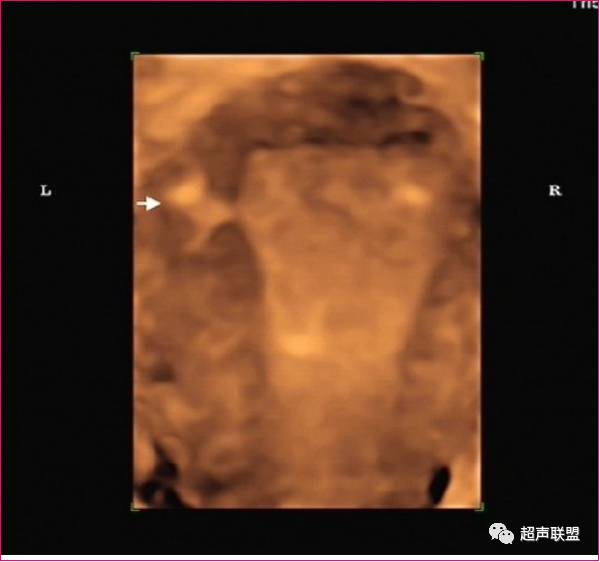

三维超声成像技术可获取二维超声不能得到的冠状面的回声信息,可以直接反映子宫外形和宫腔形态,形象完整地显示IUD的整体,清晰显示IUD有无断裂及嵌顿程度、部位。

圆形环位置下移

宫腔形环位置下移

声像特点为节育器不在宫腔内而向下移位,节育器下缘达宫颈内口或内口以下,剖宫产切口处常形成憩室,也可是节育器下移到达之处,有时节育器可下移至宫颈管内,或脱出宫颈外口至阴道。

一般节育器的上缘距宫腔底内膜以下一段距离,或上缘距宫底大于2cm即诊断为宫内节育器下移。